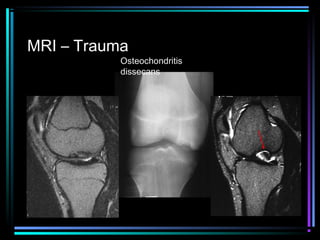

MRI – Trauma

Osteochondritis

dissecans